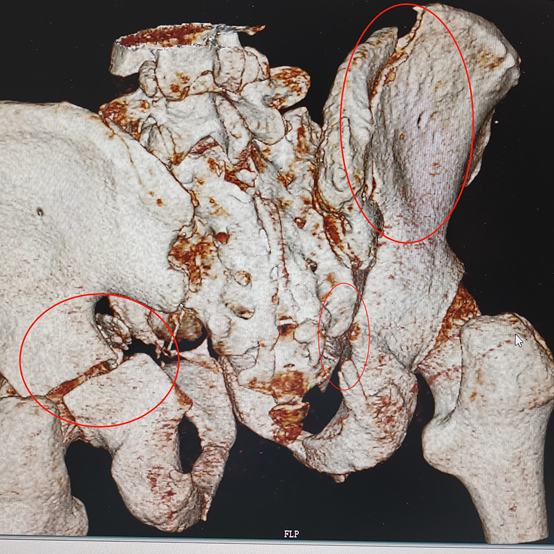

快速分析各項(xiàng)檢查結(jié)果:復(fù)雜的雙側(cè)骨盆開放性粉碎性骨折+髂內(nèi)動(dòng)脈斷裂+尿道斷裂+雙側(cè)多發(fā)肋骨骨折+雙側(cè)血?dú)庑?嚴(yán)重肺挫傷+腹部閉合性損傷+皮下大面積脫套傷+多處血腫等,出血迅猛,病情十分危急。曹飛主任、周春峰主任、介入科孫英豪主任一致認(rèn)為病情非常危急,需立即對(duì)患者進(jìn)行手術(shù),即緊急損傷控制性手術(shù)DCS(介入血管造影+栓塞+骨盆外固定+膀胱造瘺術(shù)),止血、糾正休克及控制傷情進(jìn)一步惡化。

吸痰、冰毯、抗炎、抗凝、氣管切開、下腔靜脈濾器植入……見招拆招,ICU的日日夜夜,在嚴(yán)重創(chuàng)傷并發(fā)癥的狂風(fēng)暴雨中,創(chuàng)傷中心與ICU醫(yī)護(hù)人員的精心照料,為韓大叔撐起了生命之傘。周春峰與周袁平主任節(jié)假無(wú)休,除夕前,還為韓大叔做了雙側(cè)骨盆髖臼骨折確定性手術(shù)(雙側(cè)前后路切開復(fù)位內(nèi)固定VSD引流術(shù))。

雙側(cè)骨盆髖臼骨折前后路手術(shù)